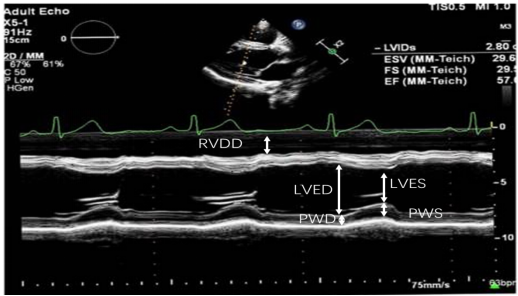

(1)左心射血分数(LVEF):最常用的一个值,通常采用心尖双平面改良Simpson法图21或者Teichholtz法(图22)测量。若有心肌节段运动异常,推荐Simpson法,在心尖四腔心切面或心尖两腔心平面,利用超声系统自带的软件,描记左心室在收缩末期和舒张末期的边界,设备自动算出LVEF值。若无心肌节段运动异常,可采用M超胸骨旁长轴切面Teichholtz法来测量,取样线垂直于室间隔和左室后壁。Teichholtz法的LVEF计算公式为:

ΔD2=(LVED2-LVES2)/ LVED2×100%

LVEF=ΔD2+(100 - ΔD2)×15%

【LVED为左室舒张期内径,LVES为左室收缩期内径】

各种方法测量的LVEF参考值通常大于50%。

图片

图22. Teichholtz法在PLAX切面测量LVEF

(2)左室短轴缩短分数FS:以M超在胸骨旁长轴切面(PLAX切面)测量,取样线垂直于室间隔和左室后壁。其参考值为25%~40%。其计算公式为:

FS=(LVED-LVES)/LVED×100%

具体参照上图Teichholtz法在PLAX切面测量LVEF的内容。